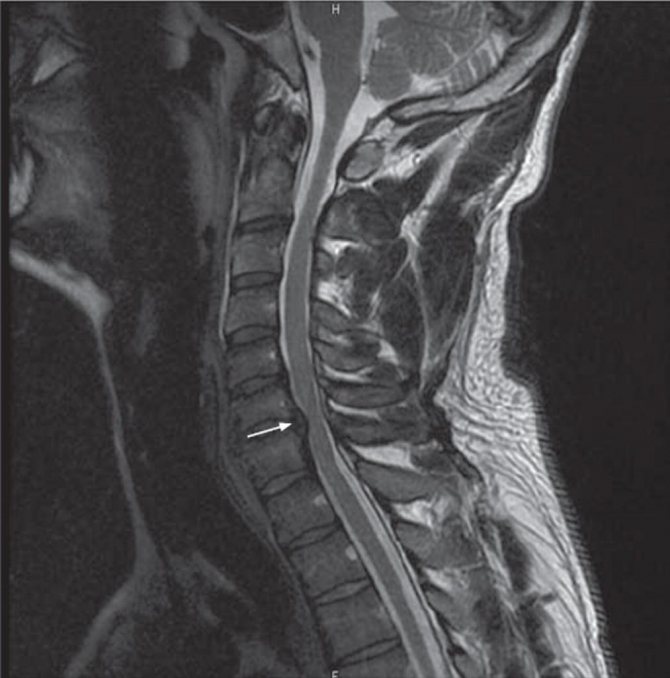

Существует несколько критериев, по которым можно классифицировать грыжу позвоночника. От точности диагностики зависит назначаемое лечение и тот факт, удастся ли достичь ремиссии и избавиться от симптомов грыжи на позвоночнике у женщин. На фото ниже — грыжа на рентгеновском снимке.

Симптомы грыжи позвоночника у женщин (фото рентгеновского снимка больного человека представлено ниже):